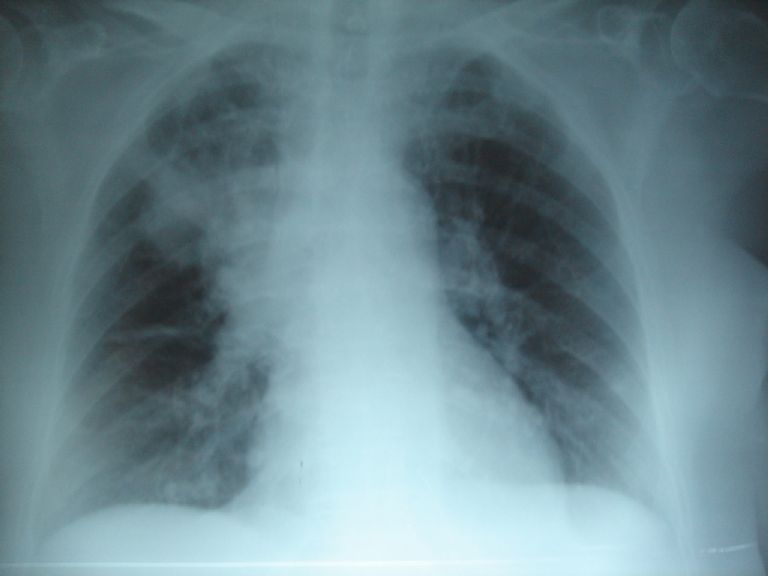

Señaló que hay casos en lo que la fibrosis se confunde con asma, debido a las dificultades que presenta el menor para respirar o las alergias, además indicó que una de las características que coadyuvan a identificar este padecimiento, son el bajo peso, neumonías recurrentes, desnutrición y diarreas.